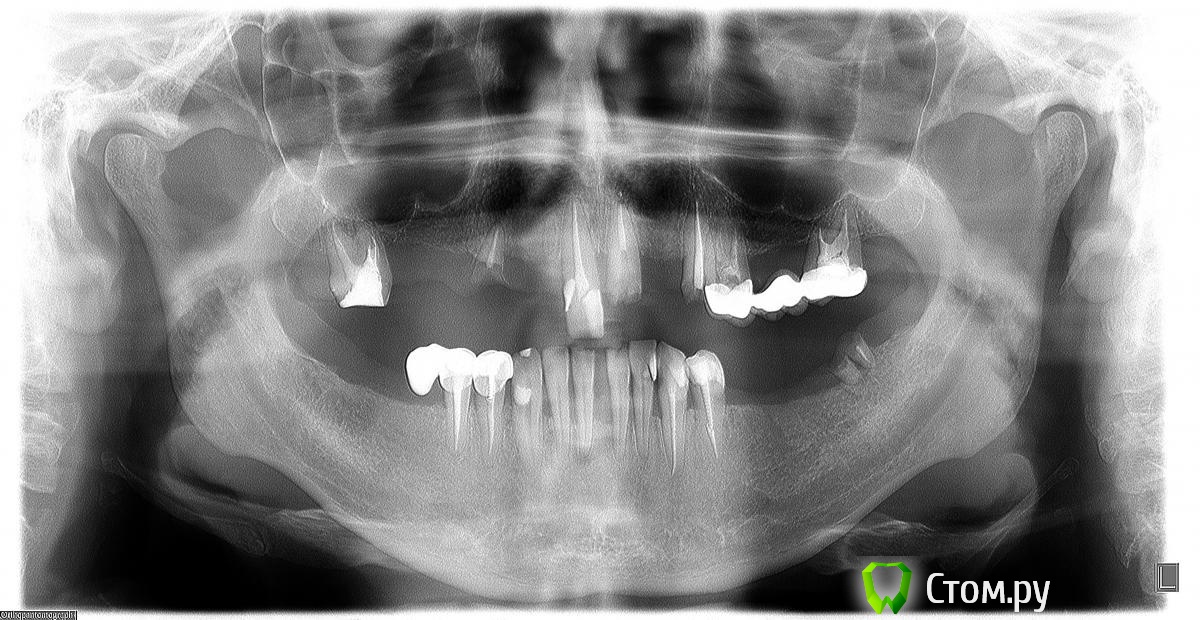

AndryLuk Опубликовано 22 ноября, 2014 Поделиться Опубликовано 22 ноября, 2014 Здравствуйте!Проконсультруйте пожалуйстаПоотваливались мосты вверху, пришлось искать в тырнэтах (т.к. цивилизация далеко) какие либо варианты восстановления зубного ряда.Нашел н-ске клинику обещающую восстановить одноэтапной импантацией. Приехал, отправил снимок, пришел ответ -"доктор посмотрел, можно сделать, примерная стоимость ......". На консультацию записали аж на 2.12.Пошел в другой центр стоматологии, в Томске, посмотрели сказали - удалить оставшиеся зубы с верхнейчелюсти - подождать 1,5 недели -потом сделают временный протез и только через 3(непомню может 4) месяцавозможно будет поставить импланты потом опять подождать 6 мес., а уж потом только протезировать.Одноэтапная сказали невозможна из-за ширины или толщины кости.Нижнюю челюсть пока не рассматриваю.Действительно через 1,5 недели можно уже сделать временный протез или дольше времени зарастают лунки?Все этапы должны быть оговорены (прописаны) в плане или договоре прежде чем начать удаление ?Какой из предложенных вариантов приемлем? Может есть третий? Удалить все зубы вроде никогда не поздно? Ссылка на комментарий

faity Опубликовано 23 ноября, 2014 Поделиться Опубликовано 23 ноября, 2014 верх удалять все, низ 3.2-4.2 и 3.7при желании можно попробовать одномоментно, но для этого надо знать толщину кости. КТ надо Ссылка на комментарий